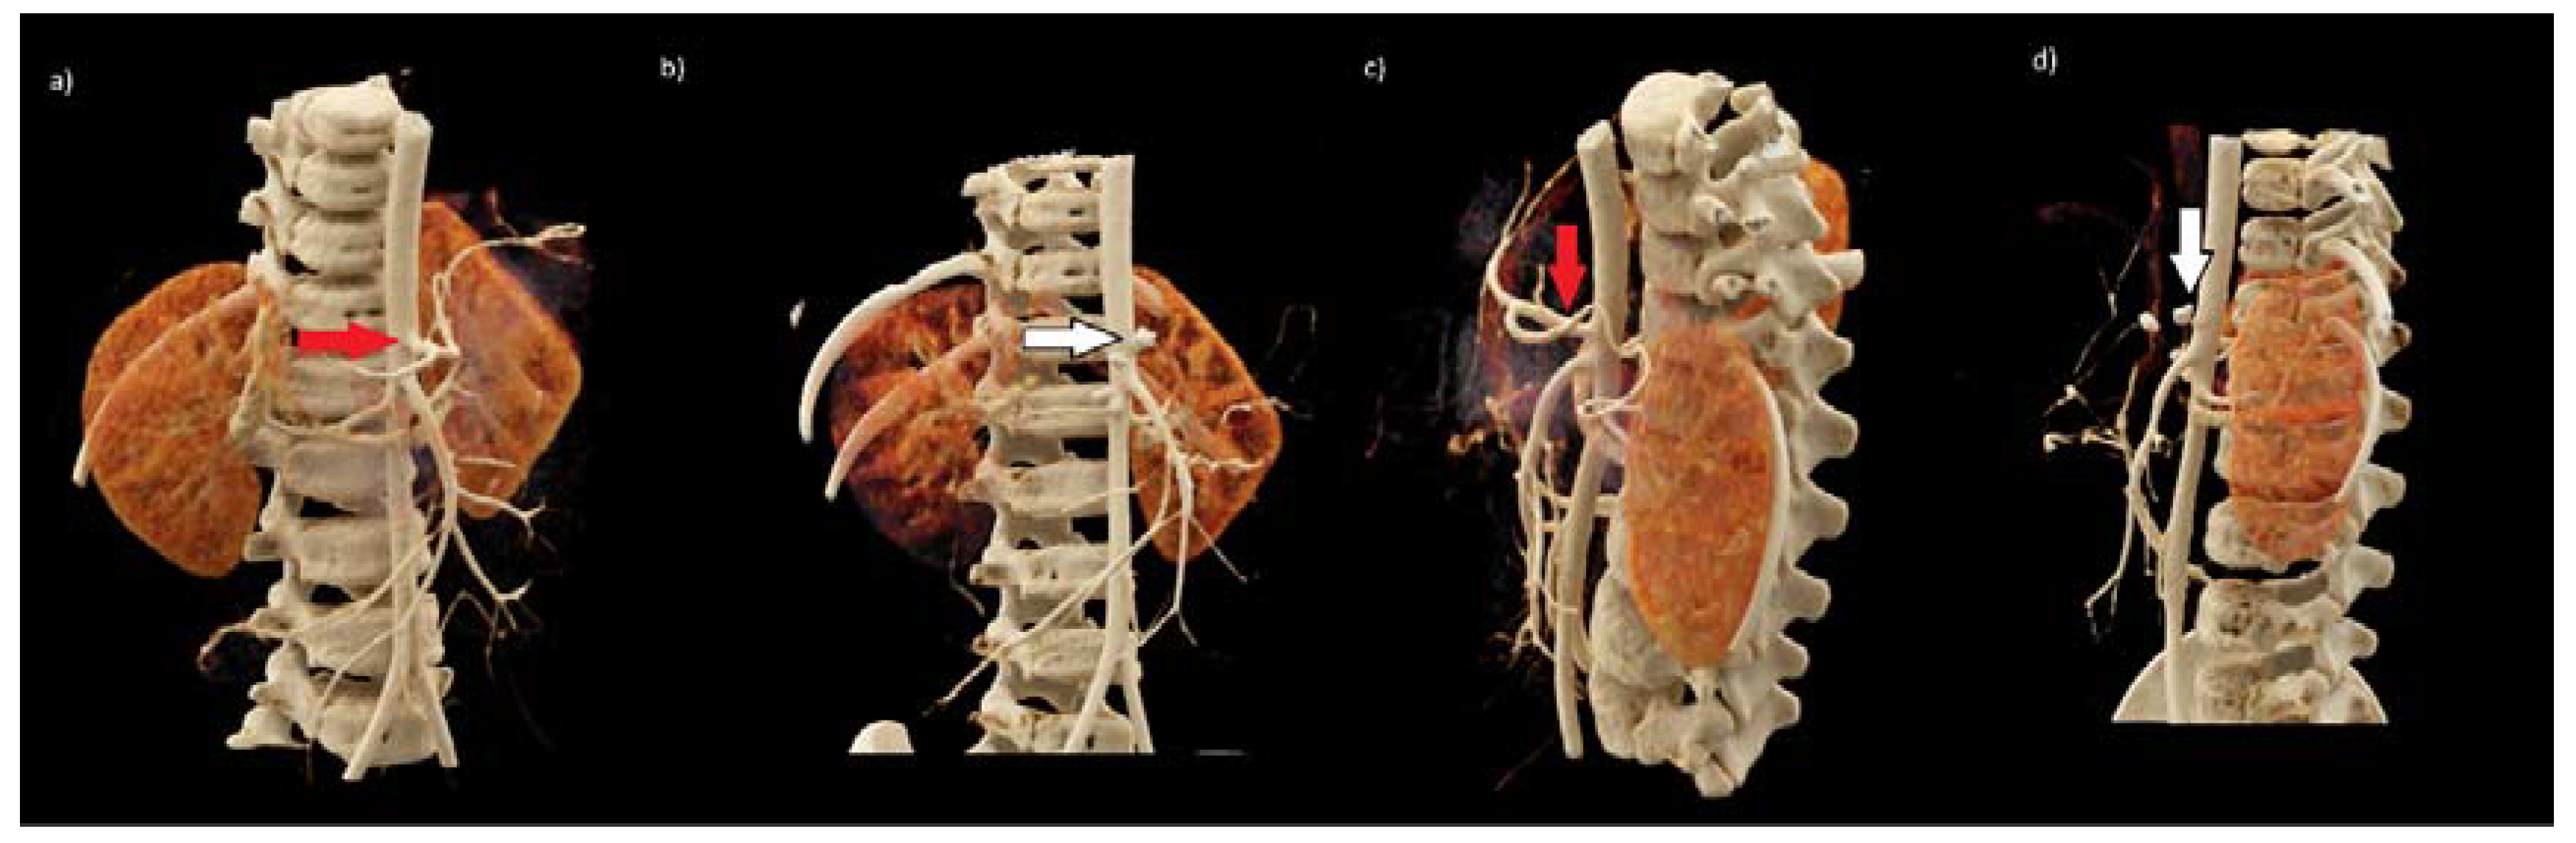

We present a retrospective analysis of the verification of radiological examinations performed on a 2.5-year-old boy with neuroblastoma. The boy was admitted to the hospital with a tumor in the abdominal cavity. Imaging examinations—ultrasonography (USG) and computed tomography (CT)—showed a solid mass, anteriorly from the right kidney and the thoracolumbar spine, ranging from Th11 to L3, with significant contrast enhancement. The lesion infiltrated the following organs: pancreas, the right adrenal gland, the liver’s visceral surface, the right kidney, the duodenum, the right side of the diaphragm, the right psoas muscle, and showing the neoplastic infiltration. The tumor compressed the inferior vena cava (VCI), which was about 2.5 cm away from the spine and was narrowed to 4 mm. Moreover, the tumor surrounded the following vessels: aorta (70–75% of the circumference), celiac trunk (100% of the circumference), common hepatic artery (100% of the circumference), superior mesenteric artery (100% of the circumference), VCI (50% of the circumference), right renal vein (50%), left renal vein (100%), splenic vein (50% of circumference), portal vein (50% of circumference). The dimensions of the lesion were: 4.9 cm × 4.6 cm × 7.3 cm (Figure 1a).

The control CT, which was performed eight weeks from the moment of diagnosis, showed the reduction of the tumor volume. The mass was 35% smaller (Figure 1b). The decision about resection with further postoperative chemo- and/or radiotherapy was made.

The INRGSS classifies neuroblastoma into the following: L1—disease is localized and does not involve vital structures, is limited to one body compartment and L2—a localized disease with positive IDRFs, M- distant metastases present, and MS- metastatic disease confined to the skin, liver, and/or bone marrow in children <18 months of age) [1]. According to the INRGSS classification, the presented patient was in group L2. Three IDRFs have been identified (the tumor encased aorta and vena cava, the origin of the celiac axis, and branches of the superior mesenteric artery at the mesenteric root) (Figure 1). That is why two cycles of chemotherapy were initially applied, resulting in a volume reduction of over 35%. Most patients in the L1 stage can be treated using surgery only. Barak et al. mentioned that 80% of the tumors, including high-risk neuroblastoma tumors, had total gross resection of the tumor with minimal operative morbidity and no mortality. Overall, 88% of children had greater than 90% resection of their lesion, and the three-year survival was 84% [3]. These results confirmed the sense of surgical treatment in our patient. Unfortunately, the postoperative complication related to the ligation of the vessel, which was identified as the vessel supplying blood to the tumor, resulted in many serious complications. In the postoperative angiography, this vessel was identified as a coeliac trunk. The coeliac artery and its branches supply blood to the spleen, pancreas, liver, stomach, and part of the duodenum. The precise knowledge of the localization of the celiac trunk in context to the tumor represents an essential prerequisite for the successful removal of the tumor [4,5]. Our patient presented type 1 of coeliac trunk variation (Figure 4).

Figure 1. Axial abdominal computed tomography scan in venous phase showed a retroperitoneal tumor in our patient a diagnosis (a) and after two courses of chemotherapy with Vepeside and Carboplatin (b). Abbreviations: CT—coeliac trunk, CHA—common hepatic artery, SA—splenic artery, IVC—inferior vena cava, Tu-tumor.